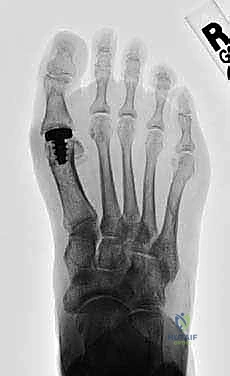

3. استبدال المفصل (Arthroplasty) - الثورة الطبية

- لمن تصلح؟ للمرضى في المراحل المتقدمة (2، 3، وأحياناً 4) الذين يرفضون دمج المفصل ويرغبون بشدة في الحفاظ على حركة المفصل.

- ما هي؟ استبدال أسطح المفصل التالفة بمواد صناعية. وهنا تبرز التقنية الأحدث والأكثر نجاحاً عالمياً: **تقنية Arthrosurface